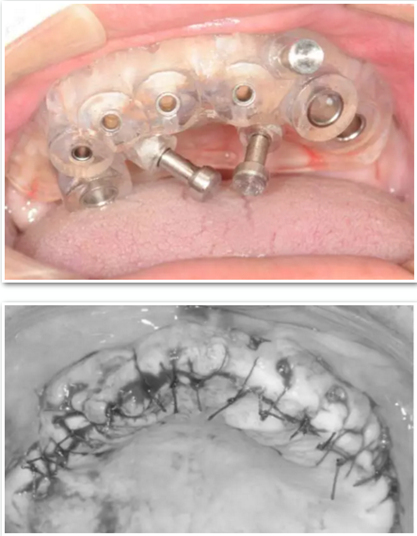

臨床手術(shù)

手術(shù)時(shí),帶上導(dǎo)板,逐級(jí)備孔,在15和25的位置需要進(jìn)行內(nèi)提升,因此對(duì)于備孔深度的把控尤為重要,導(dǎo)板的作用得到了重大發(fā)揮。

去掉導(dǎo)板,進(jìn)行上頜竇內(nèi)提升,填入骨粉,植入種植體。

最后縫合。